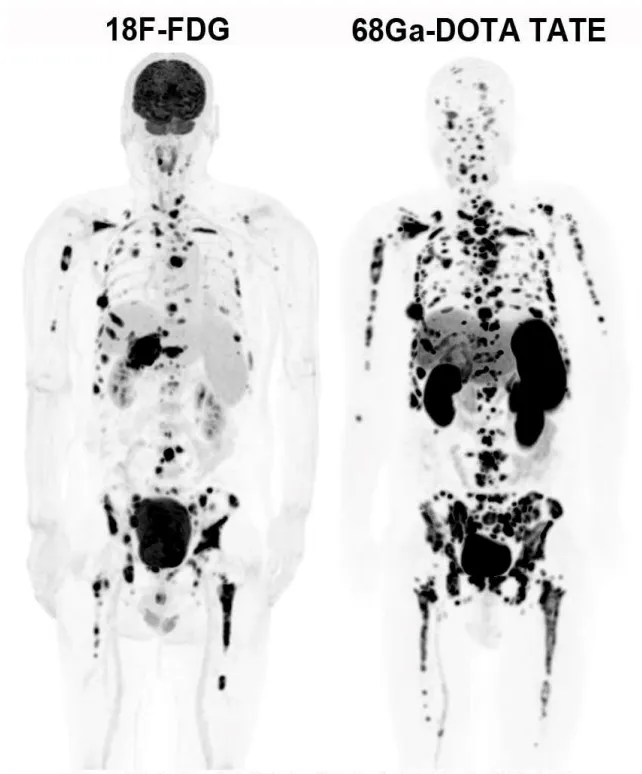

3.神经内分泌肿瘤检查(68Ga-DOTATATE):专门针对神经内分泌肿瘤(比如某些胃肠胰肿瘤、类癌等),能准确找到肿瘤位置,判断严重程度和治疗效果。

△神经内分泌癌骨骼多发转移